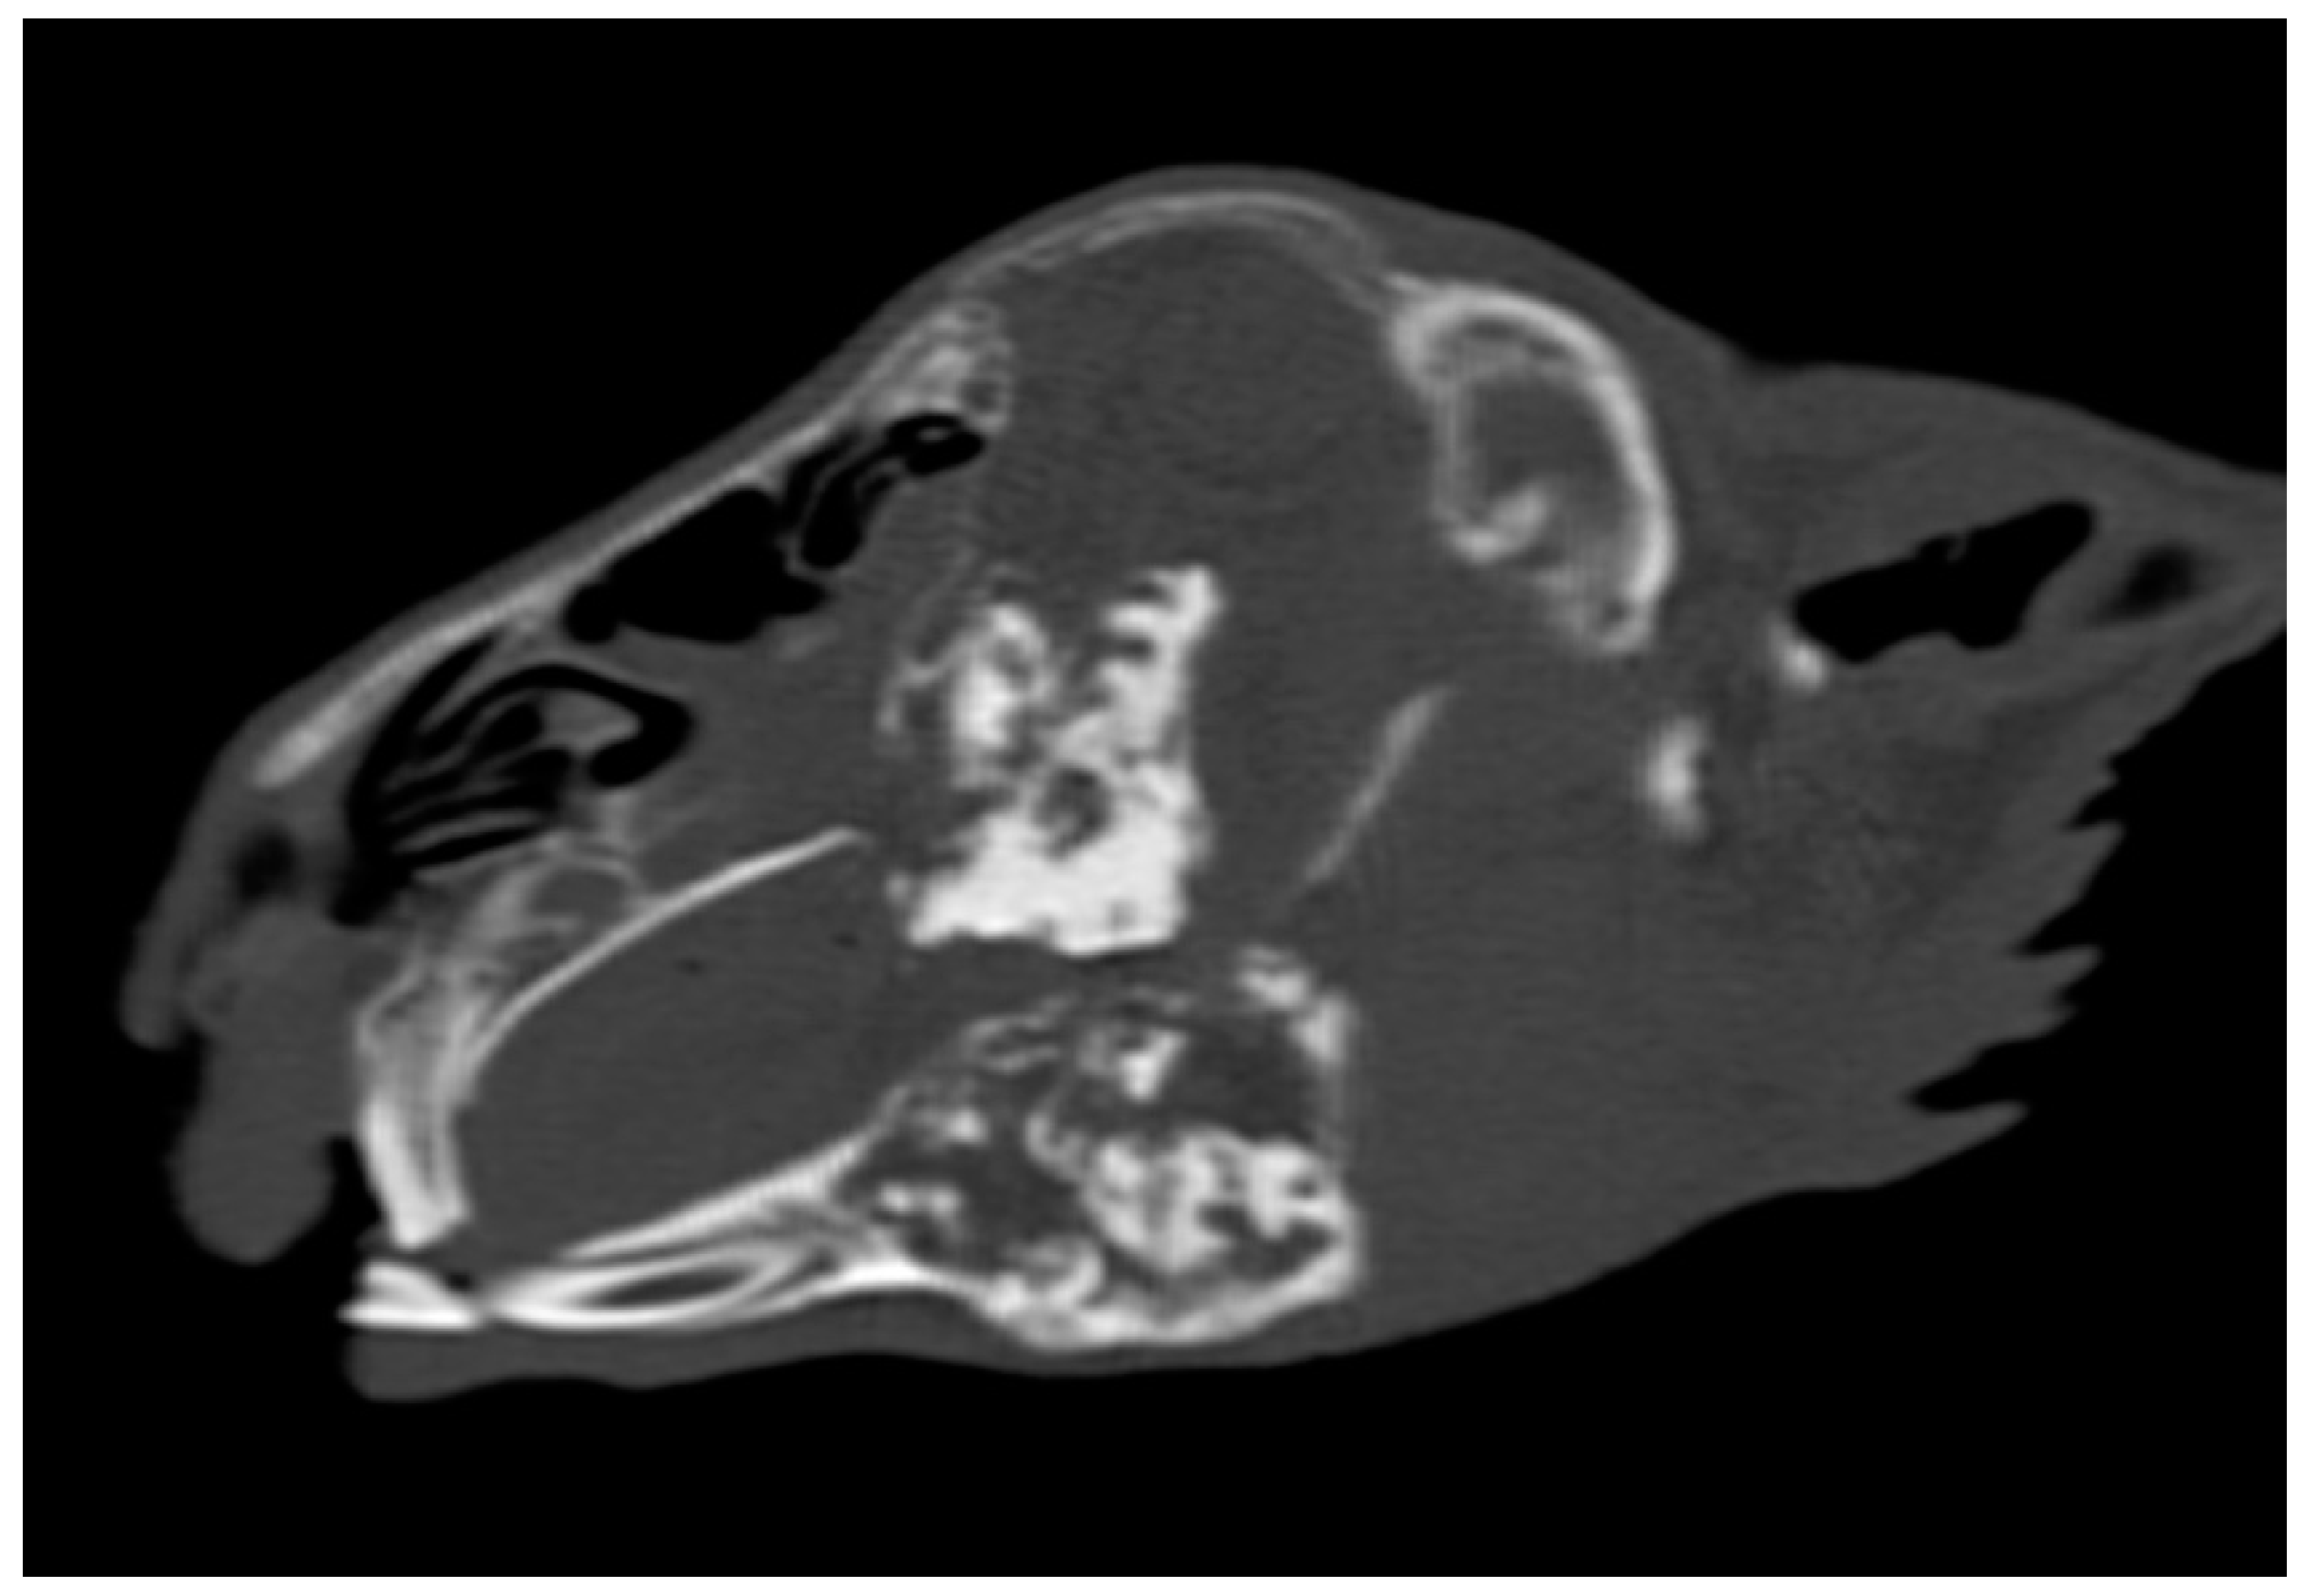

3.5. Incidence of Dental Abscesses and Secondary Osteomyelitis